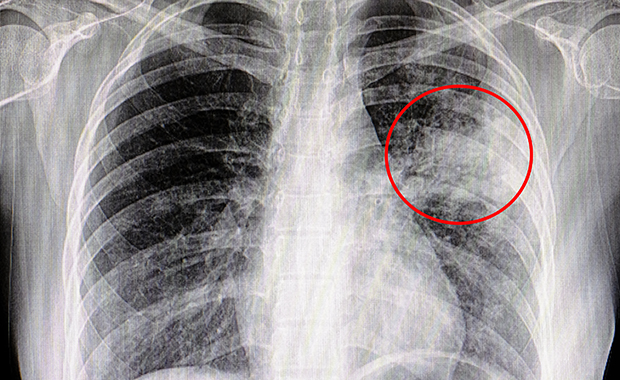

肺炎は、細菌、ウイルス、または真菌によって引き起こされる肺の感染症です。片方または両方の肺の気嚢の炎症が特徴です。肺胞とも呼ばれる嚢は液体または膿で満たされており、発熱、咳、または呼吸困難を引き起こす可能性があります。